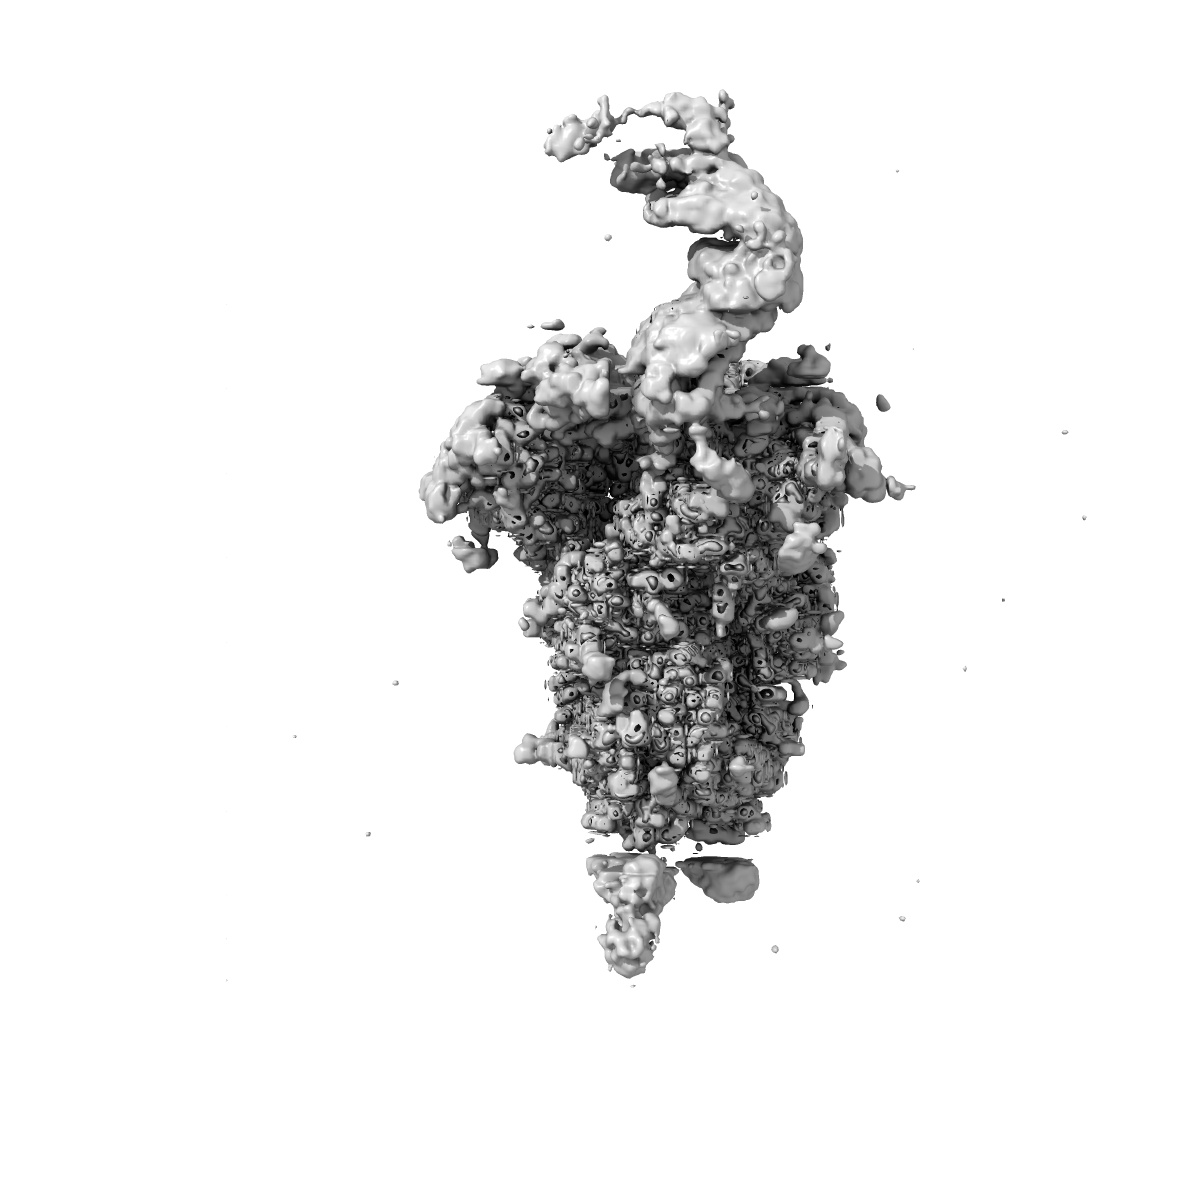

Structure of HCoV-HKU1C spike in the functionally anchored-1up conformation with 1TMPRSS2

Single-particle3.26 Å

Sample: HKU1B-TMPRSS2 complex

TMPRSS2 and glycan receptors synergistically facilitate coronavirus entry.